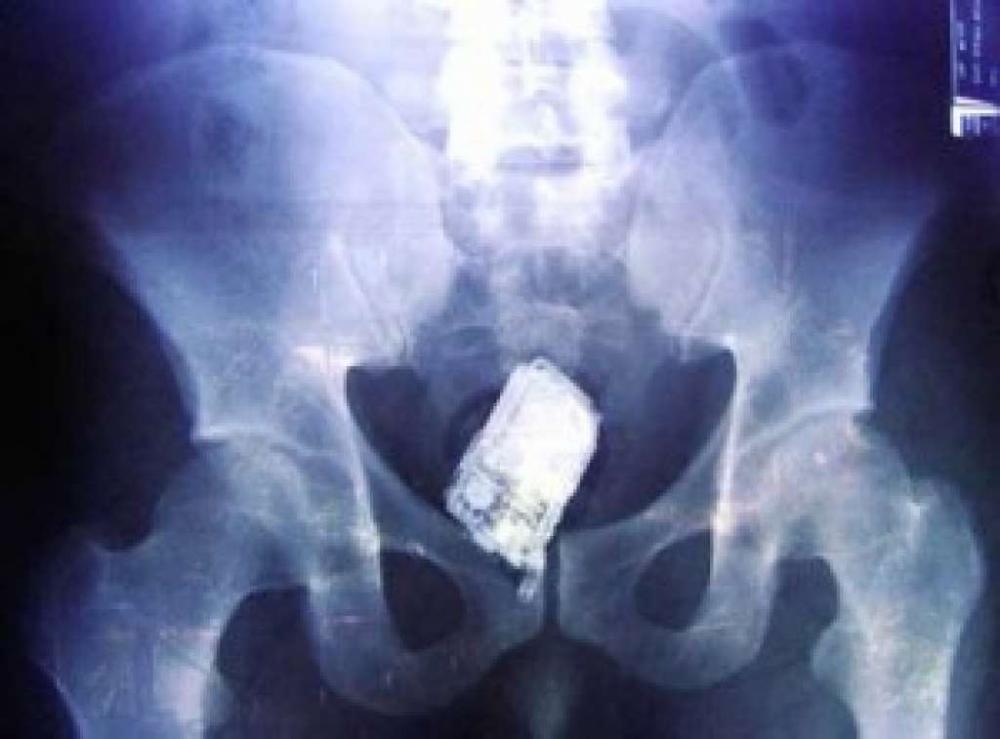

CASO INUSITADO

Há 2 anos

Jovem Passa por Cirurgia para Retirada de Celulares no Ânus em Governador Valadares

Caso inusitado mobiliza equipe médica; suspeita de tentativa de entrada em unidade prisional.